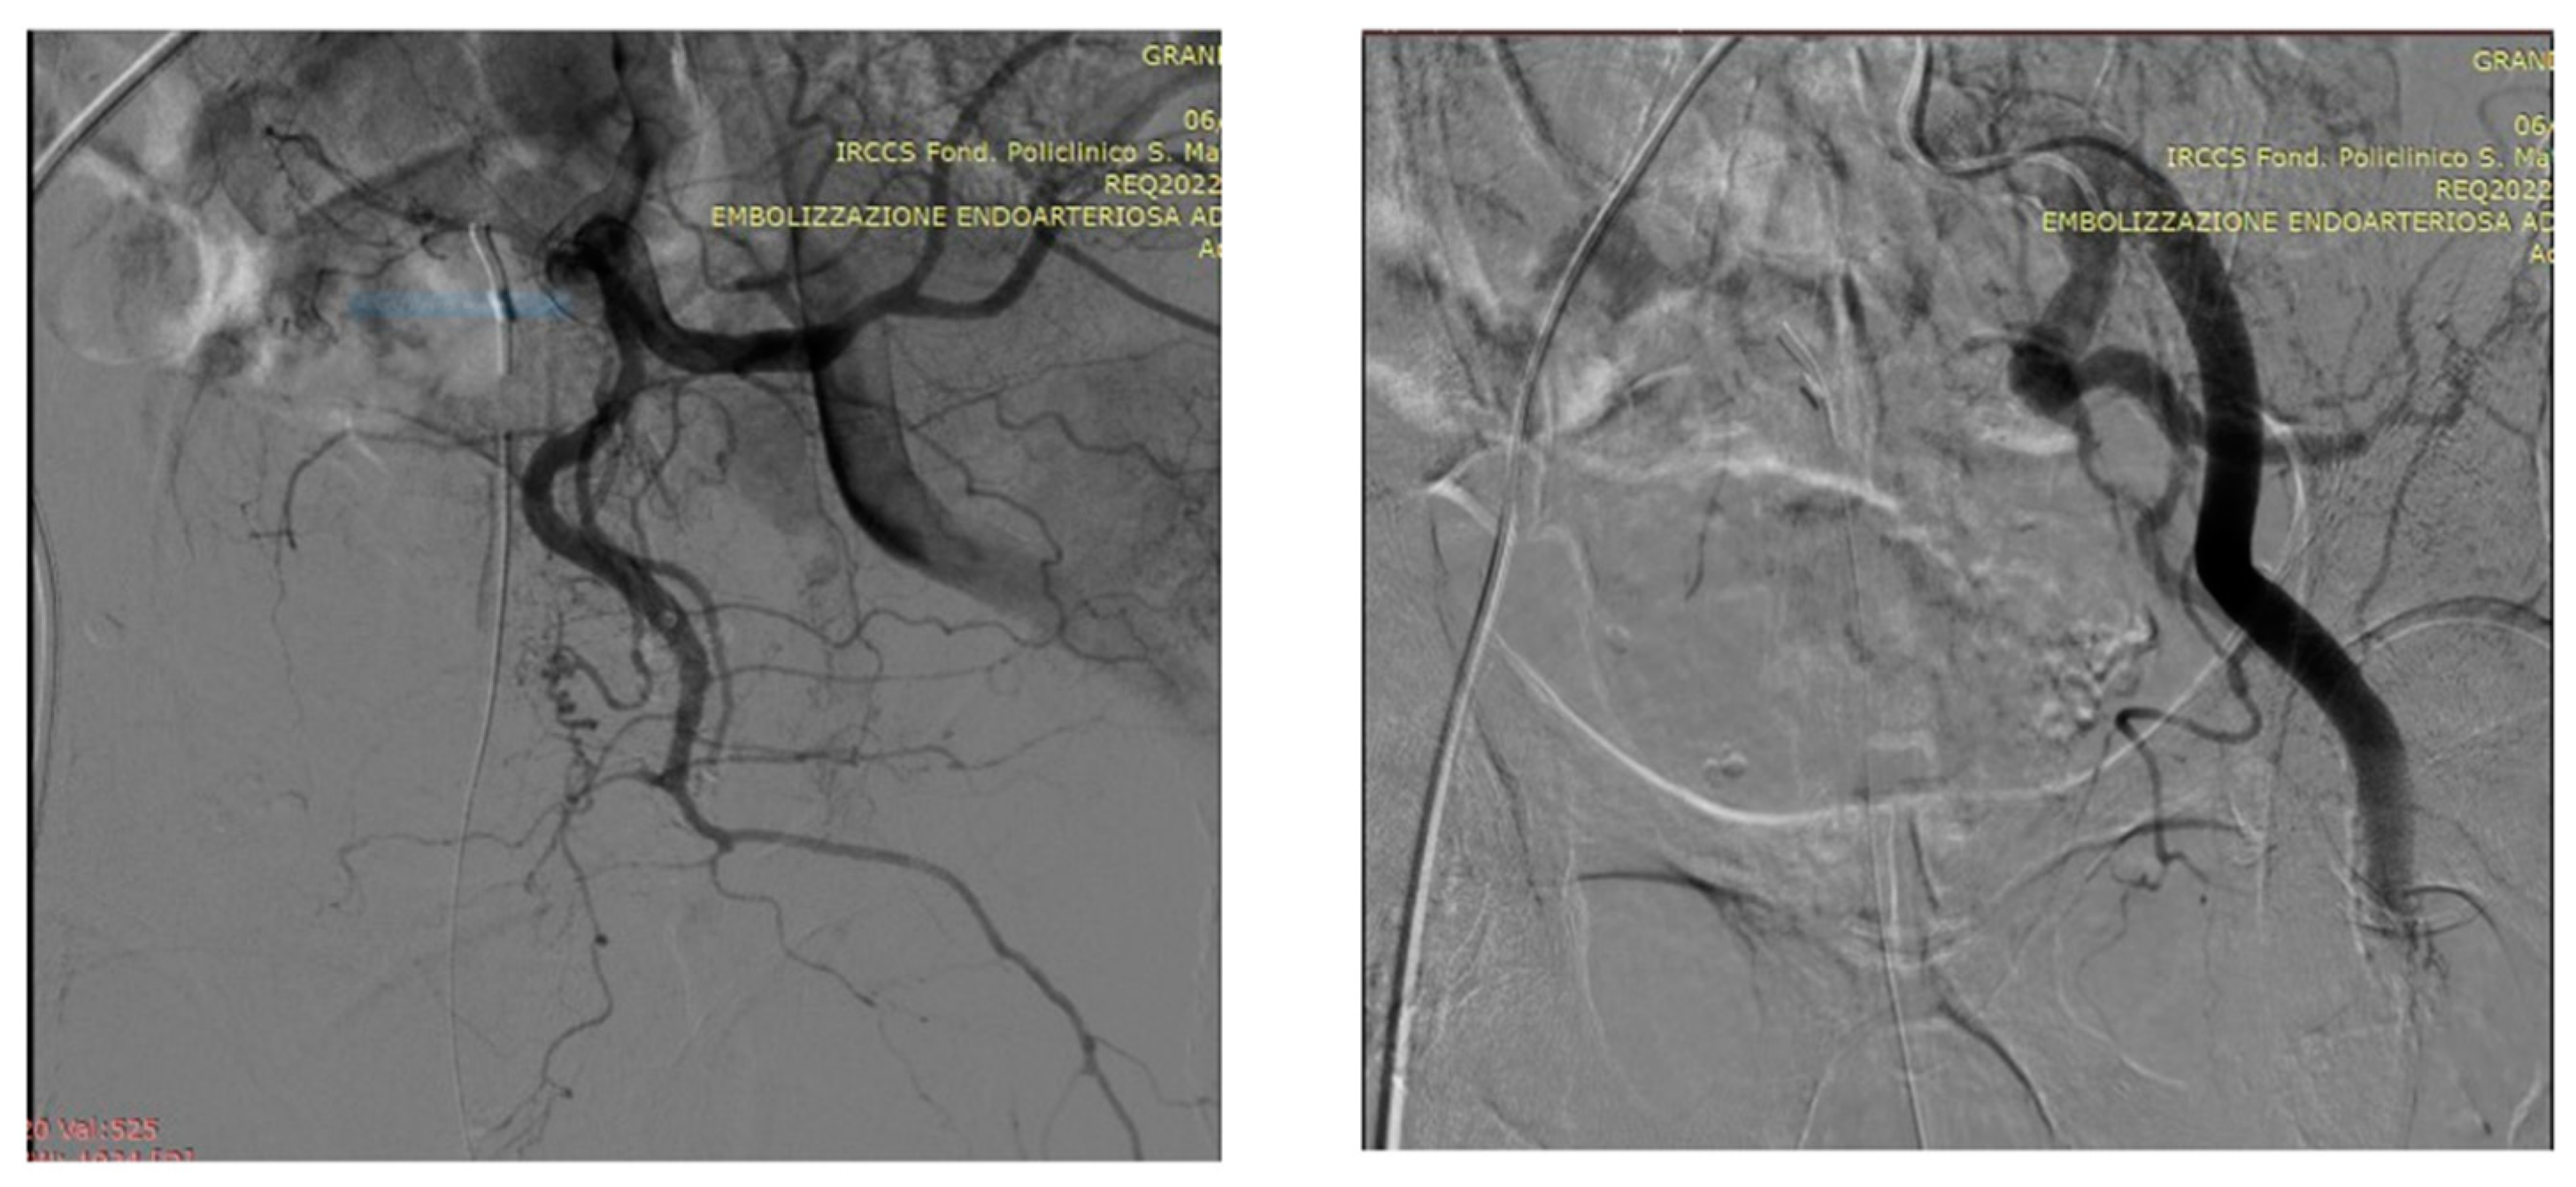

5.1. Technical details of PAE